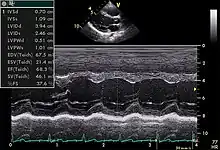

Motion mode is infrequently used in modern echocardiography. It has specific uses and has the benefit of very high temporal fidelity (e.g., measuring LV size at end diastole).